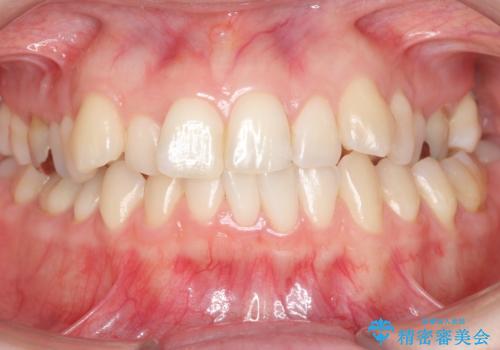

矯正歯科治療 → 叢生(でこぼこ・八重歯)

インビザラインによるガタつきの矯正治療 シンプル・短期間

前歯がガタガタ・噛み切りにくい インビザラインによる歯を抜かない矯正

Invisalign インビザラインによる軽度なガタつきの改善